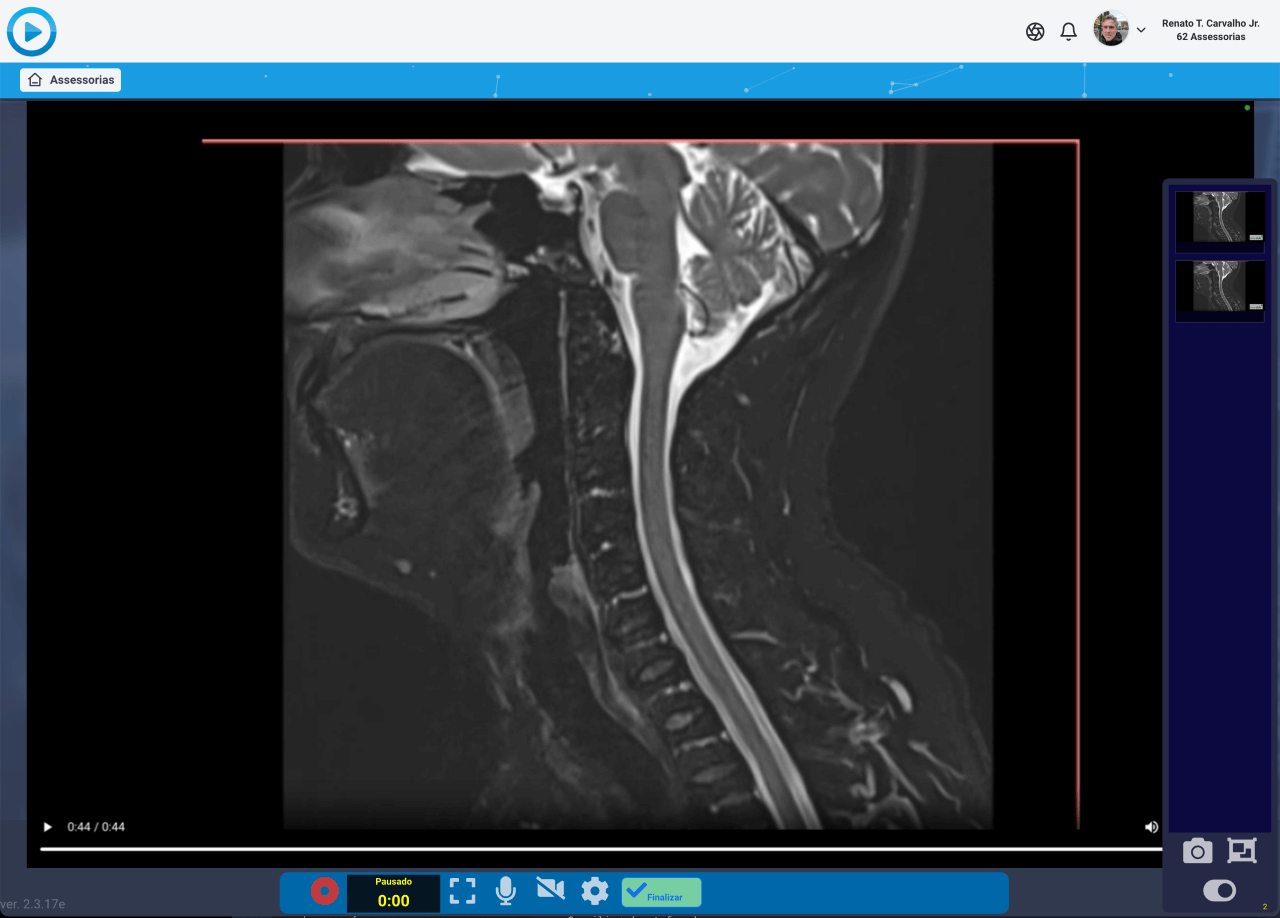

Crie laudos audiovisuais em minutos.

Com nossa poderosa ferramenta de captura de tela, você pode gravar vídeos e adicionar pontos de interesse, desenhos, textos e áudios com muita facilidade, proporcionando uma experiência objetiva e prática, sem desperdiçar tempo.